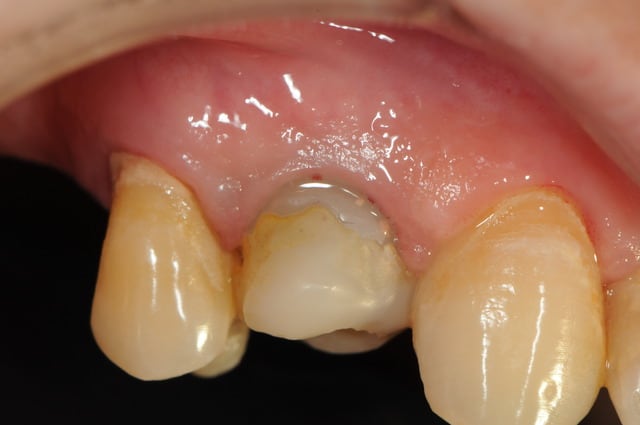

çà manque un peu de cas en ce moment...alors en voilà un ptit au passage...

11 avec résorption interne

EII avec MCI sur du dentium (4.5/14) comblement du gap vestibulaire avec du kasios tcp (très constant dans les résultats...et très économique)

pas de photos de chir par contre...j'ai du les effacer par erreur...grrrr...

la prothèse d'usage a été réalisée par ma petite associée...mais j'étais là pour superviser et faire quelques photos...;-)

chose qui a été faite dans ce cas...désolé j'ai perdu les photos de la chir, on ne voit que la phase prothétique

le biomat est du kasios tcp, on voit quelques granules qui s'éliminent de la gencive

une série de photo le jour de la pose, puis 15j après (prothèse réalisée par mon confrère)